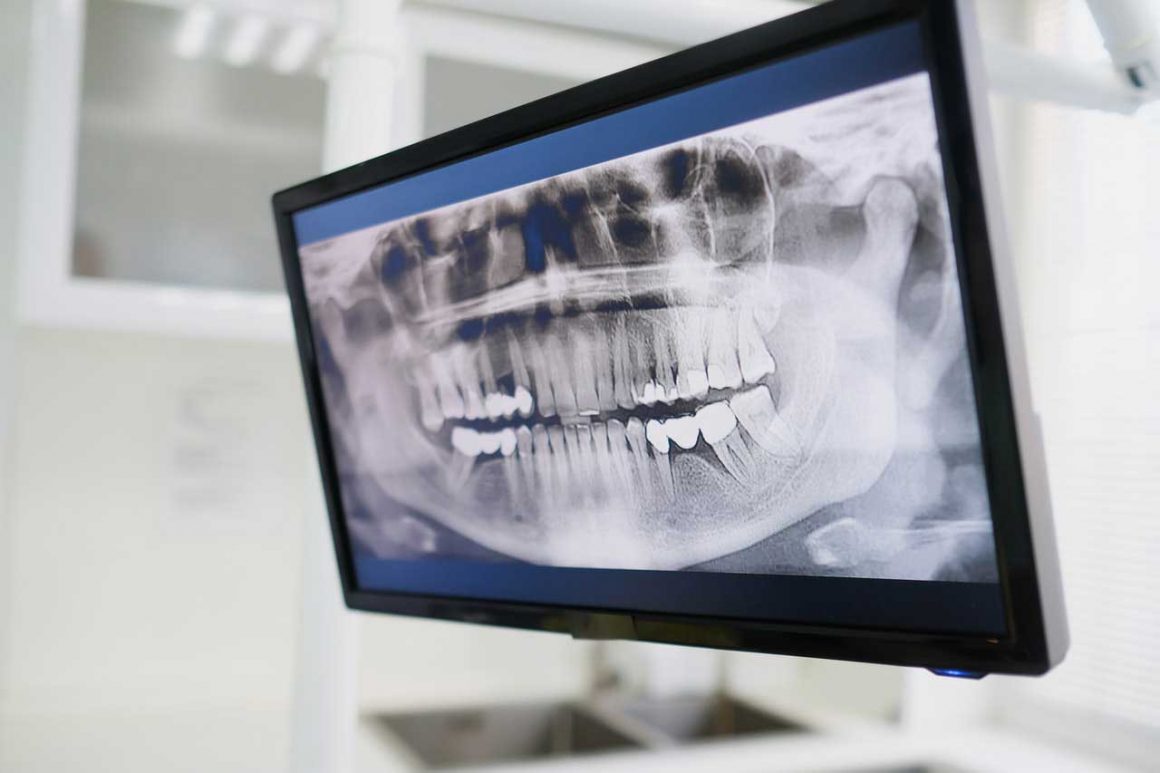

Щелепно-лицева хірургія